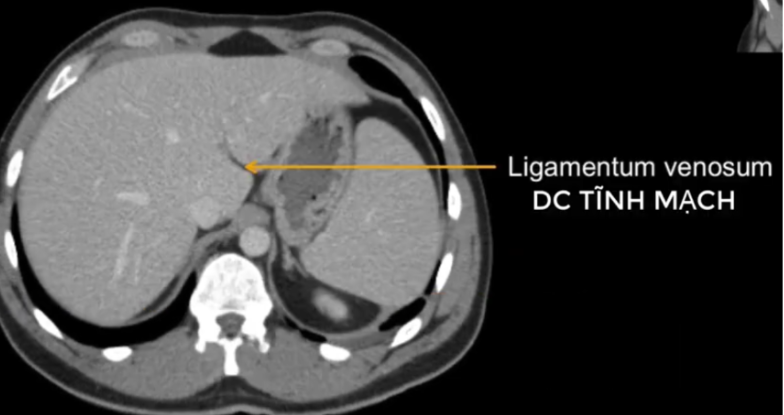

cq trong hình ?